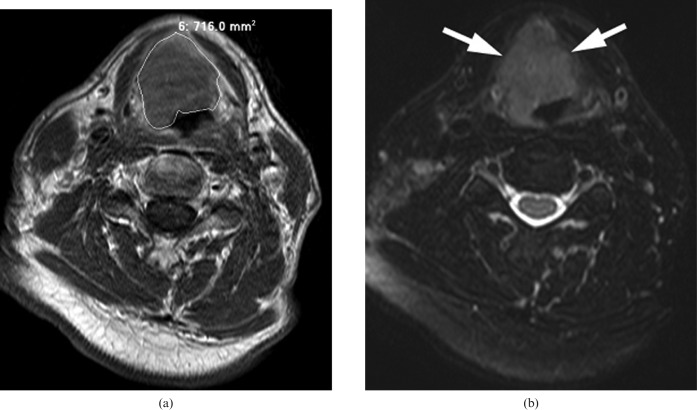

MRI examinations were retrospectively reviewed on the imaging workstation by two observers (KSSB, ADK) in consensus; these observers have 19 and 4 years' specialist experience in head and neck cancer imaging, respectively. Reviewers were blinded to the final outcome during the assessment of MRI examinations. Primary tumour volumes were measured using a summation-of-areas technique in which the tumour was manually contoured on the MRI workstation on successive axial T1 weighted post-intravenous gadolinium MR images; the summed areas of contours were then multiplied by the slice interval plus thickness (0.4 cm). In this respect, other imaging planes and sequences including T1 weighted pre-contrast, T2 weighted and fat saturation sequences were used to assist in anatomical localisation (Figure 1). Areas of obvious peritumoural inflammation and frank tumoural necrosis were specifically excluded from the contoured volume. Absolute values of tumour volume at the three time-points were documented and percentage reductions in tumour volume at 2 weeks into CCRT and 6 weeks after CCRT, compared with the pre-treatment volume, were calculated.

Figure 1.

(a) A supraglottic cancer is contoured on an axial T1 weighted post-gadolinium MRI sequence. (b) An axial T2 weighted MRI sequence with fat suppression at the same level is used to assist in anatomical localisation (arrows).